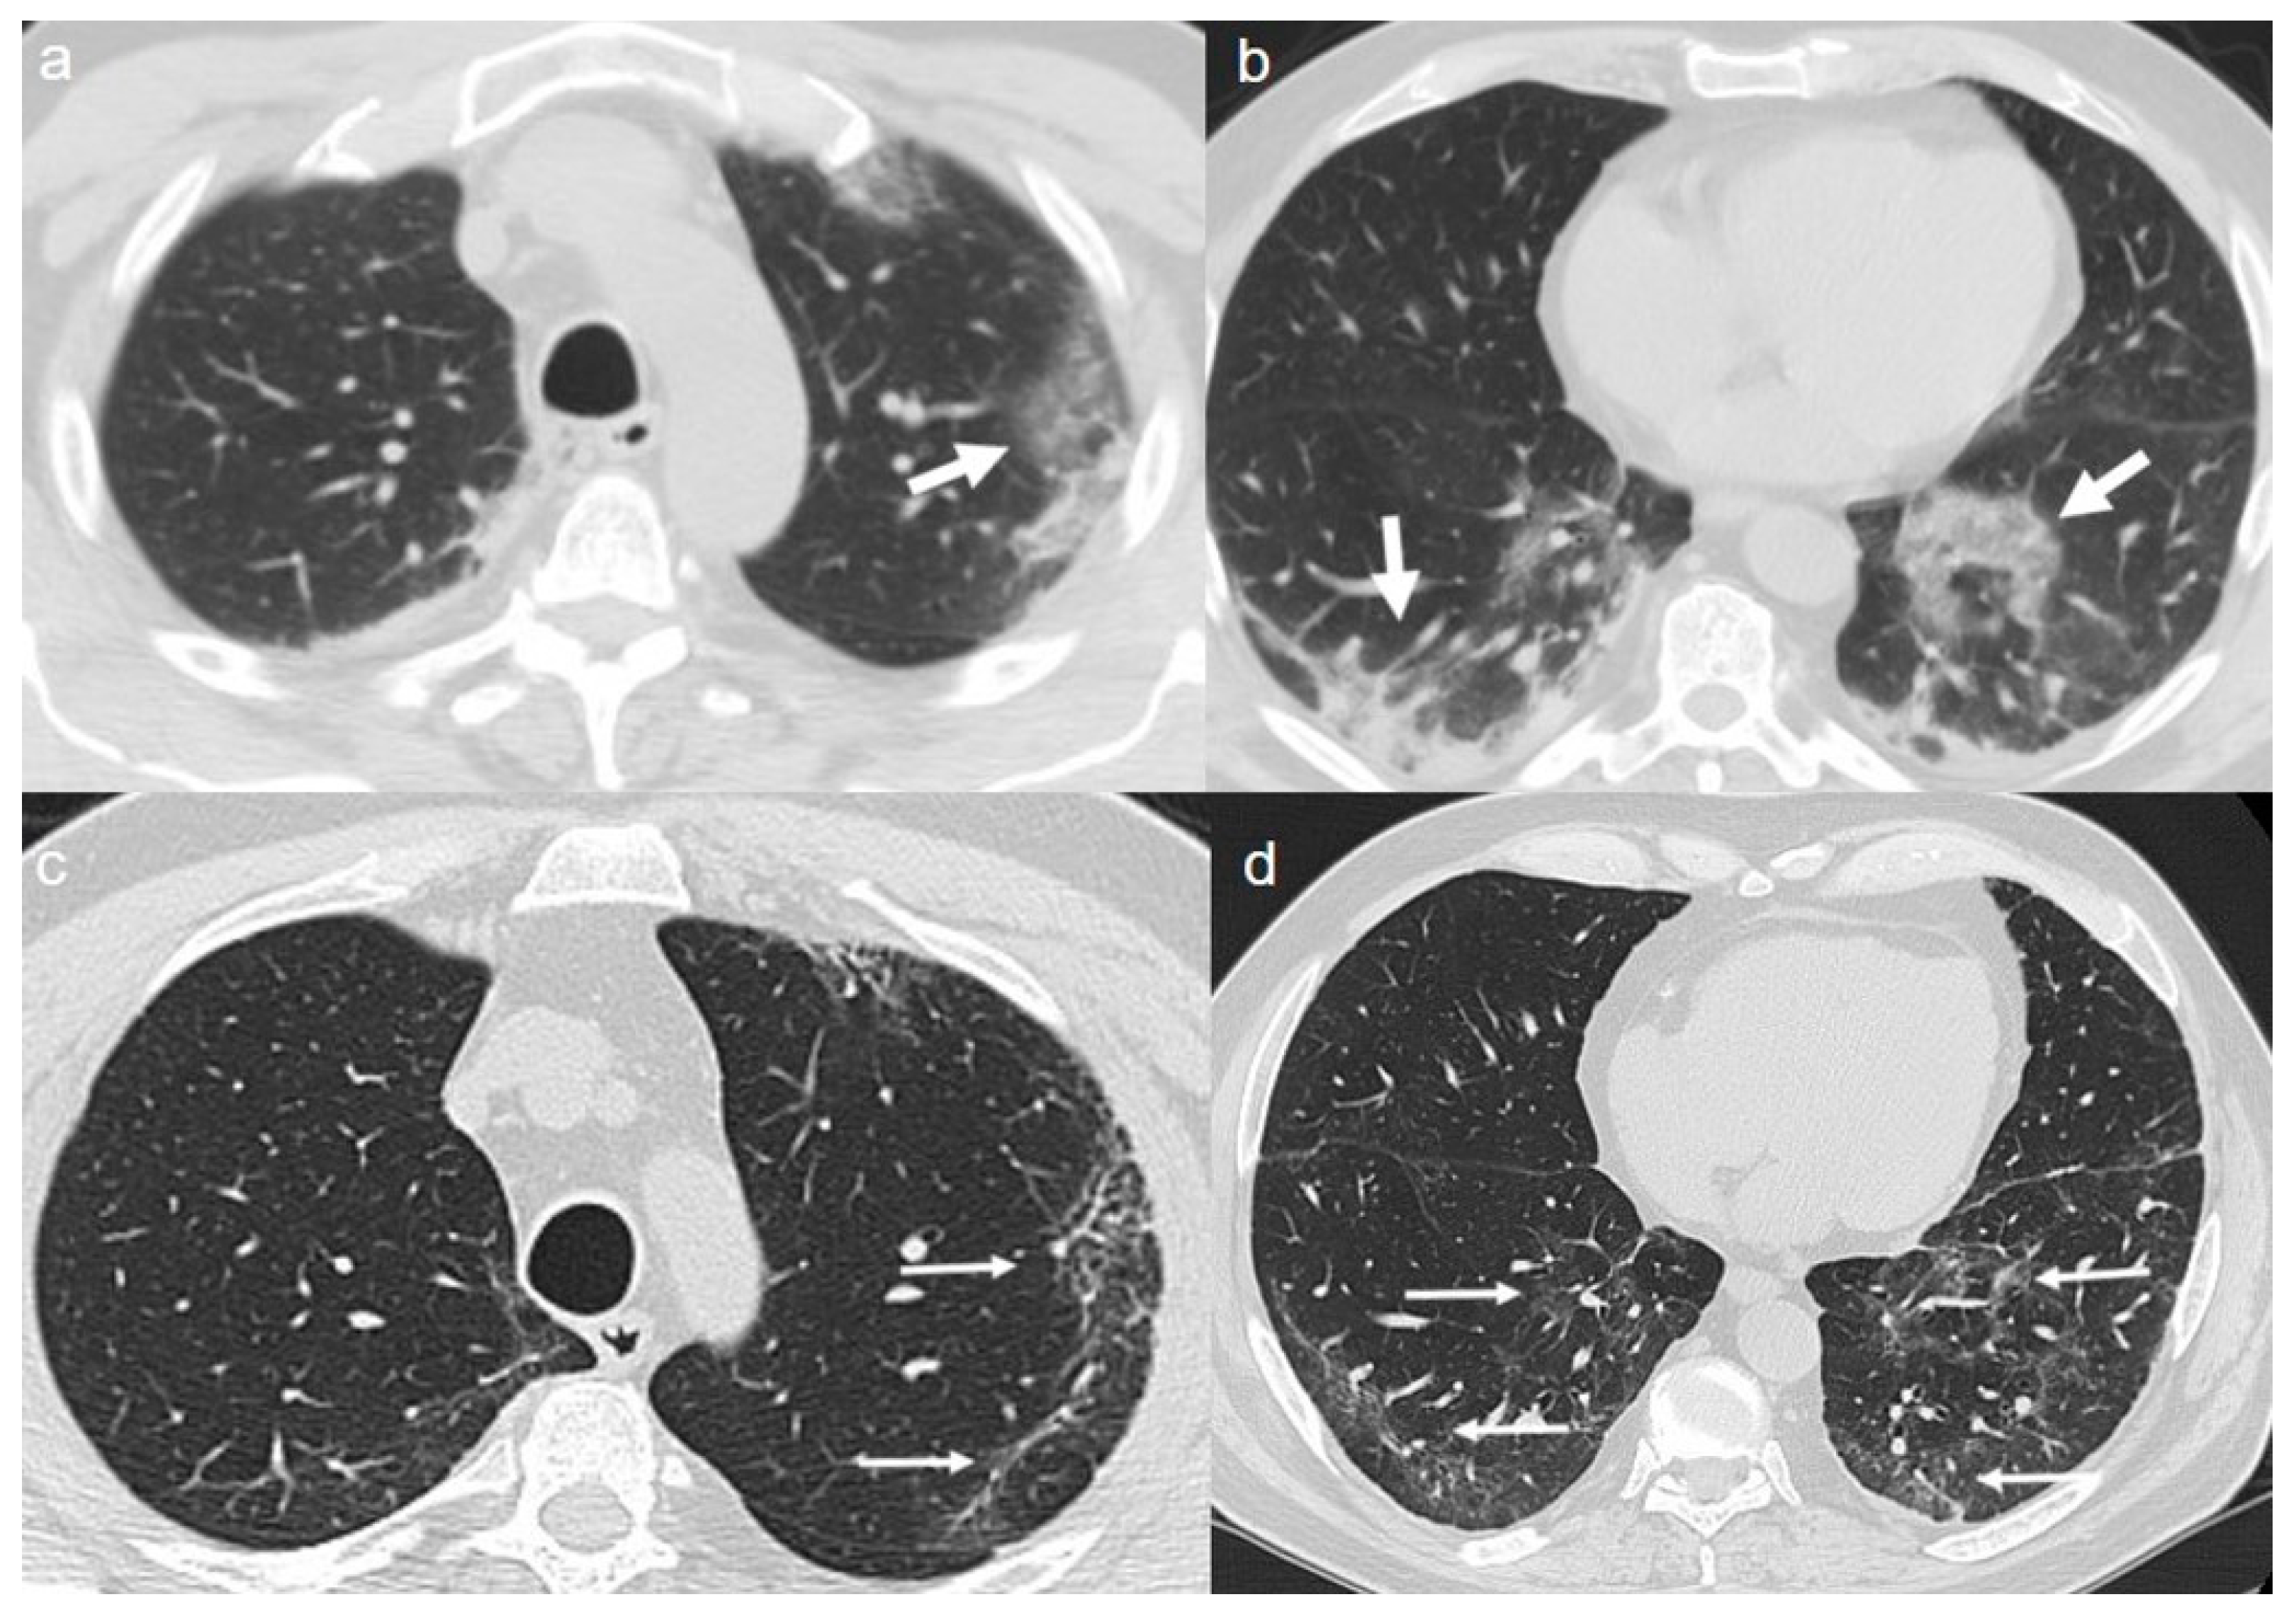

On admission, chest CT showed a “crazy paving pattern” peripherally located in the upper left lobe and in the lower lobes (Figure 6a,b).

(a,b) CT shows a “crazy paving pattern” peripherally located in the upper left lobe (arrow in a) and in the lower lobes (arrows in b). (c,d) CT after 4 months from the onset of symptoms shows persistence of mixed pattern characterized by interlobular septal thickening (thin arrows in c) and patchy GGOs (thin arrows in d).

A CT at 4 months from the onset of symptoms showed bilateral persistence of mixed pattern characterized by interlobular septal thickening and patchy GGOs (Figure 6c,d).

On admission, chest CT showed bilateral extensive areas of GGO and consolidations, with prevalent peripheral distribution in the upper and lower lobes (Figure 7a–c).

(a–c) CT shows bilateral extensive areas of GGO and consolidations, with prevalent peripheral distribution, in upper and lower lobes (arrows). (d–f) Follow up CT 4 months after admission shows persistence of diffuse thickening of the interlobular septa, with fibrotic appearance (thin arrows in d,e); air bubble sign with bronchiectasis (thin arrows in f) is recognizable.

A CT at 4 months from the onset of symptoms showed the persistence of diffuse thickening of the interlobular septa, with fibrotic appearance (Figure 7d,e); air bubble sign with bronchiectasis (Figure 7f) was also recognizable. An air bubble sign consists of a small air-containing space that can result from a dilatation of a physiological space or from lung cystic changes or can be related to consolidation resorption.